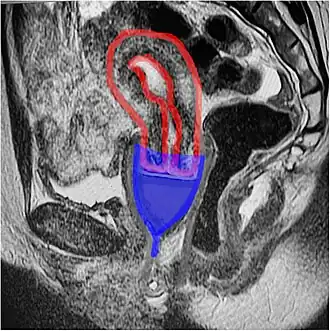

An MRI showing a bell-shaped menstrual cup in place; cup in blue, uterus in red. The ectocervix (the portion of the cervix that protrudes into the vagina) sits inside the cup. Sagittal plane.

An MRI showing a bell-shaped menstrual cup in place; cup in blue, uterus in red. The ectocervix (the portion of the cervix that protrudes into the vagina) sits inside the cup. Sagittal plane.

While many diagrams show bell-shaped menstrual cups very low in the vagina, with the vagina gaping open, in-vivo imaging shows that the cups sit high, with their rim around the cervix, and the vagina squishes shut below the cup, sealing it inside the body.[7]

Because bell-shaped cups are commonly depicted as being placed in the vaginal canal, well below the cervix, they are also called "vaginal cups", with the ring-shaped cups called "cervical cups". This may not clearly reflect their position in the body. MRI imaging suggests that, contrary to some manufacturer's depictions, the bell-shaped cups called "vaginal cups" are placed over the cervix, in a position similar to a cervical cap (not to be confused with a cervical cup).[7] Ring-shaped cups, called "cervical cups", also cover the cervix, but have one edge next to the cervix, and the other located further down the vagina, so that the cup is nearly parallel to the long axis of the vagina.[24]